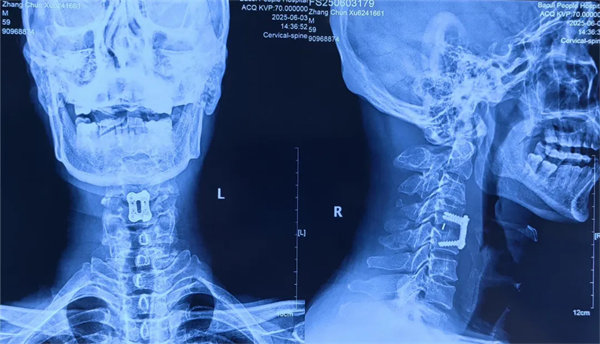

術(shù)后

患者受傷后曾在外院接受保守治療,但肢體麻木癥狀持續(xù)存在。轉(zhuǎn)入我院時,頸椎CT及MRI顯示:頸4/5椎骨折脫位,脊髓受壓明顯,若不手術(shù)治療,可能面臨永久性神經(jīng)功能障礙。我院骨四科團(tuán)隊(duì),制定了前路ACDF手術(shù)方案:通過頸前側(cè)入路,切開復(fù)位、切除椎間盤,解除脊髓壓迫,同時植入融合器、鈦板固定,重建頸椎正常序列及穩(wěn)定性。術(shù)后患者麻木感消失,復(fù)查顯示頸椎序列恢復(fù)良好,目前已康復(fù)出院。